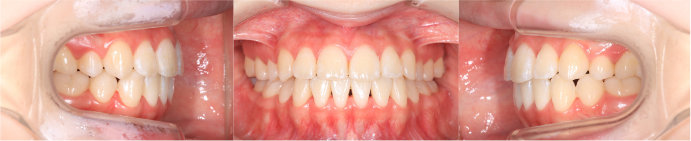

| Case5 |

| 前歯のガタガタ |

| <治療前> |

| <治療後> |

| 主訴 |

上下の前歯の乱れが気になる |

| 診断名 |

叢生 |

| 年齢 |

10歳 |

| 使用装置 |

マルチブラケット装置 |

| 抜歯部位 |

永久歯の抜歯は無し |

| 治療期間 |

2年6か月 |

| 治療費概算 |

検査・診断料:5万円+税 装置・技術料:25万円+税 おおよそ1か月ごとの処置・管理料:5,000円+税 保定装置料:5万円+税 |

| リスク・副作用 |

特になし |